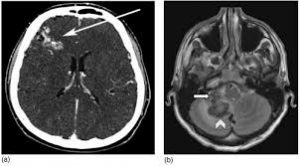

Chẩn đoán xác định bằng cách chụp hình ảnh tĩnh mạch và xác định rằng các cục máu đông nằm trong các xoang tĩnh mạch.

Chụp cắt lớp vi tính tĩnh mạch đồ hoặc chụp cộng hưởng từ tĩnh mạch đồ được thực hiện để giúp cho chẩn đoán.

Chụp cắt lớp vi tính (CT Scan), chụp cộng hưởng từ (MRI).